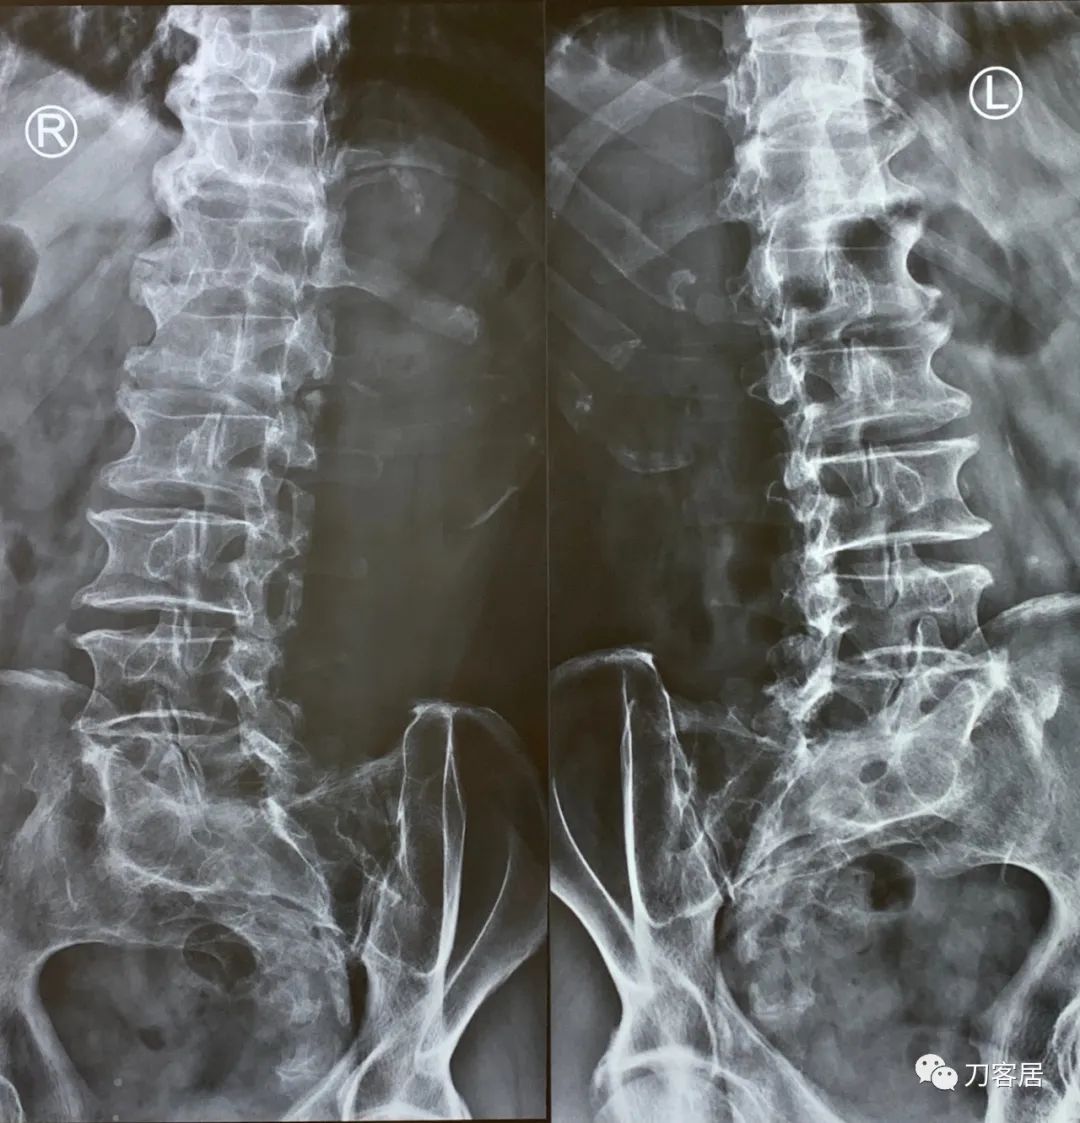

详细听完患者的就诊过程和病史,结合这次患者来就诊的主要诉求是右下肢右足麻木半年,考虑到患者有腰5峡部裂,腰5椎体滑脱,所以,建议拍摄腰椎6位片,复查一下腰椎滑脱的情况是否有加重,骨密度检查看一下有无骨质疏松。

图20. 20221116西京医院腰椎正侧位X线片

图21. 20221116西京医院腰椎过伸过屈位X线片

图22. 20221116腰椎双斜位X线片

图23. 20221116西京医院腰椎6位X线片报告

很遗憾,这次我们医院放射科的读片医生,竟然没有诊断腰5峡部裂和腰5椎体滑脱。通过本病例的X线片报告,也说明,即使是对于同一患者的影像学资料,不同的放射科医生,也会有不同的解读。